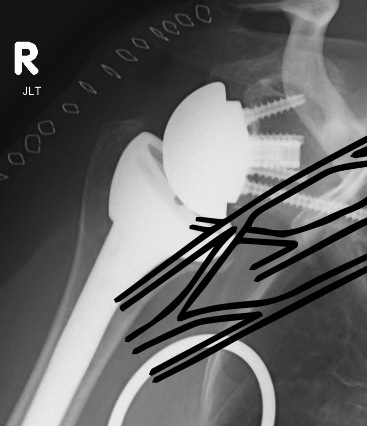

Humeral shaft fractures

Hum shafthum shaftHum shaft

Stable humeral component treated with ORIF

hum #Hum #Hum #

Unstable humeral component